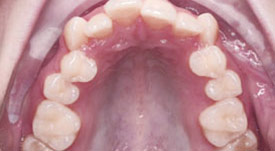

Crowding Upper